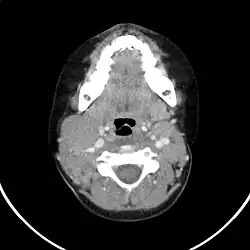

Computertomographie des Halses bei hochmalignem Non-Hodgkin-Lymphom der Halslymphknoten (Transversalschnitt mit Kontrastmittel).